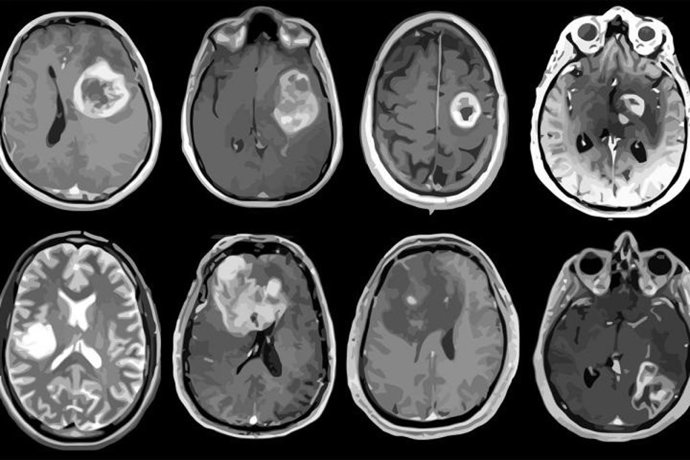

Archivo - Glioblastoma, tumor cerebral agresivo mapeado en detalle genético y molecular.

Archivo - Glioblastoma, tumor cerebral agresivo mapeado en detalle genético y molecular. - ALBERT H. KIM - Archivo